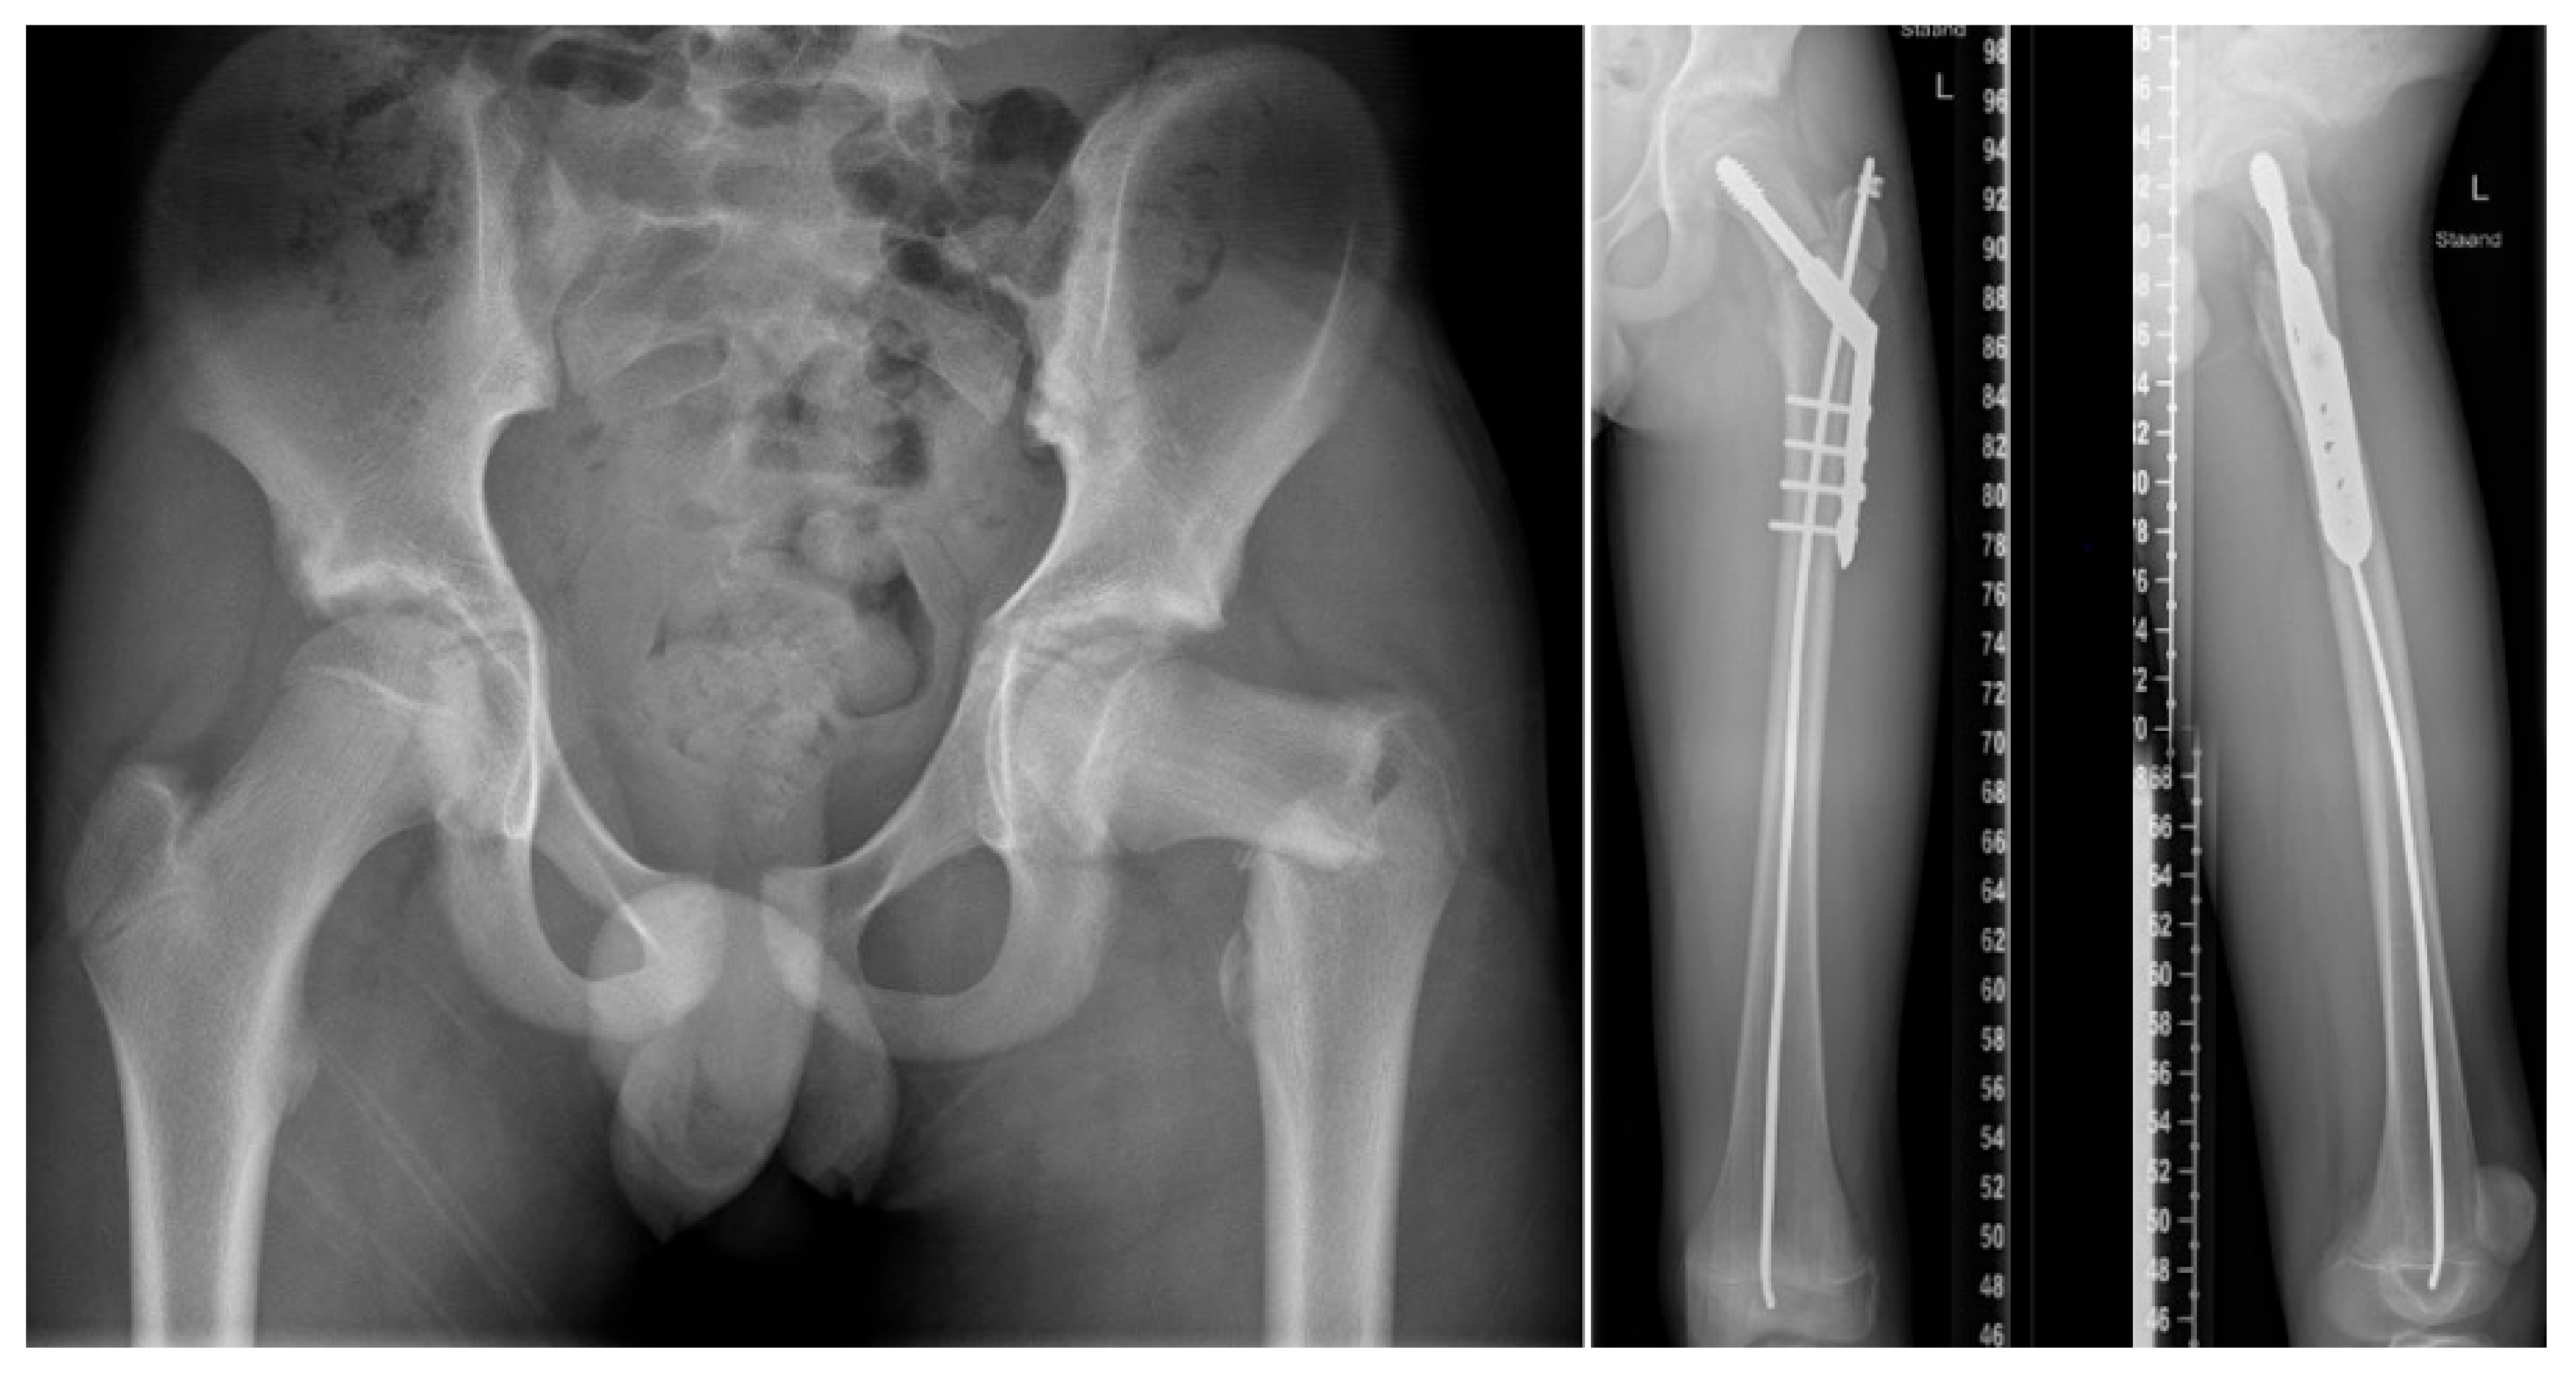

4. Fracture Management

5.3. Preventive Surgery

- Azzam, K.A.; Rush, E.T.; Burke, B.R.; Nabower, A.M.; Esposito, P.W. Mid-term Results of Femoral and Tibial Osteotomies and Fassier-Duval Nailing in Children With Osteogenesis Imperfecta. J. Pediatr. Orthop. 2018, 38, 331–336. [Google Scholar] [CrossRef]

- Sakkers, R.J.; Montpetit, K.; Tsimicalis, A.; Wirth, T.; Verhoef, M.; Hamdy, R.; Ouellet, J.A.; Castelein, R.M.; Damas, C.; Janus, G.J.; et al. A roadmap to surgery in osteogenesis imperfecta: Results of an international collaboration of patient organizations and interdisciplinary care teams. Acta Orthop. 2021, 92, 608–614. [Google Scholar] [CrossRef]